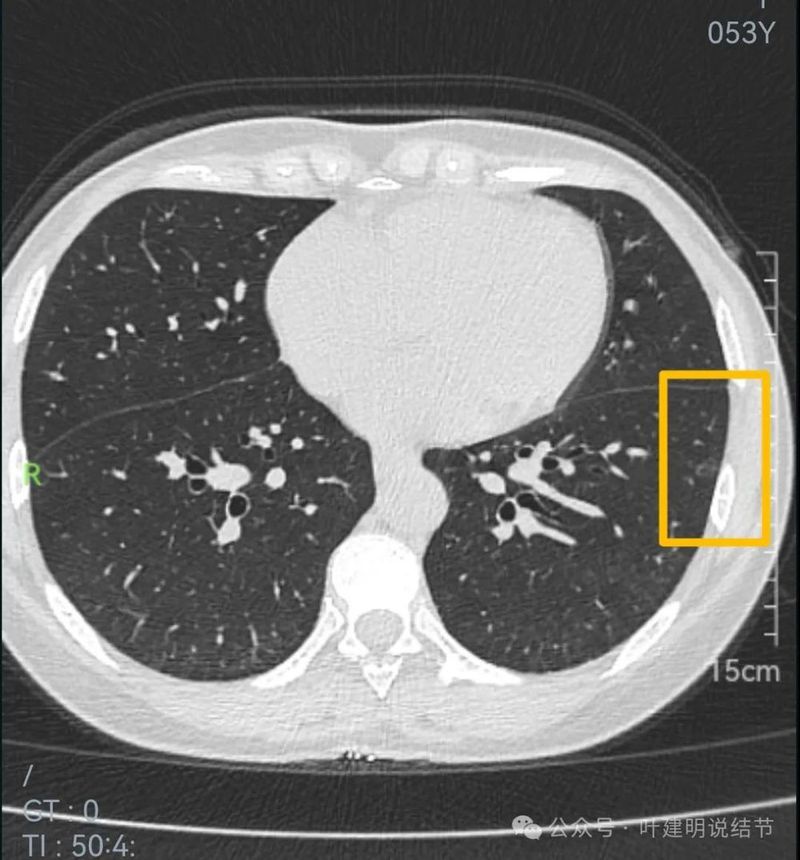

红色的实性结节缺乏膨胀性,位于胸膜下,两侧多发,考虑良性的;黄色的密度过淡,也不是典型结节状,大概少许纤维增生或肺泡上皮增生可能性大,目前风险小;粉色的磨玻璃密度,轮廓与边界清楚,考虑肺泡上皮增生或不典型增生可能性大。总体可年度复查随访。意见供参考!